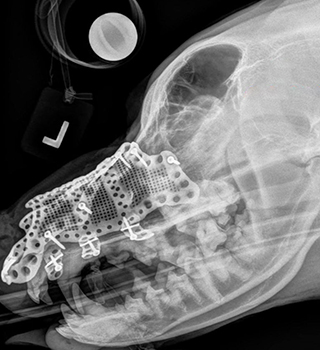

A seven-year-old Bernese Mountain Dog with a tumour on the left side of his maxilla (upper jaw) had few options other than total excision of the growth followed by reconstruction. A customised 3D printed titanium implant supporting the dog's bone structure was the most appropriate treatment due to the complexity of the region, requiring significant design and manufacturing freedom.

Without additive manufacturing technology, it would have been impossible to reconstruct the dog's maxilla after tumour removal, because the area was extremely complex in geometry.

The procedure, which was carried out by Julius Liptak, veterinary surgeon at Alta Vista Animal Hospital in Ottawa, Canada, used an additively manufactured titanium maxillofacial implant designed by Voxelmed, based in Germany.

During the design of the implant, Dr. Liptak reviewed the design repeatedly to compare it to 3D scans and models of the dog's skull. This made the process of manufacturing and placement much more straightforward, as it met the surgeon's specifications for how the implant would fit.

“During surgery, the affected areas, along with clean tumour margins, were removed,” explained Jan Klasen, veterinary surgeon, 3D designer and CEO of Voxelmed. “Because the tumour occurred in the skin, rather than the maxillary bone, resection involved a revision maxillectomy with excision of the 45 mm x 50 mm mass, with 30 mm lateral margins. The implant was then put into place and fixed with surgical screws. A facial axial pattern skin flap was prepared and used to cover the affected area and the implant. This left the dog with a particularly impressive physical outcome as the nose structure did not have to be altered to account for the missing tissue.

Without additive manufacturing technology, it would have been almost impossible to reconstruct the dog's maxilla after tumour removal, because the area was extremely complex in geometry,” Klasen commented. “The implant had to have a similar shape and functionality as the dog's existing bone structure. Using additive manufacturing to maintain the original shape and function of the oral and nasal cavity ensures a high quality of life for the dog, just as a naturally shaped skull and maxilla helps the dog to breathe and eat easily.